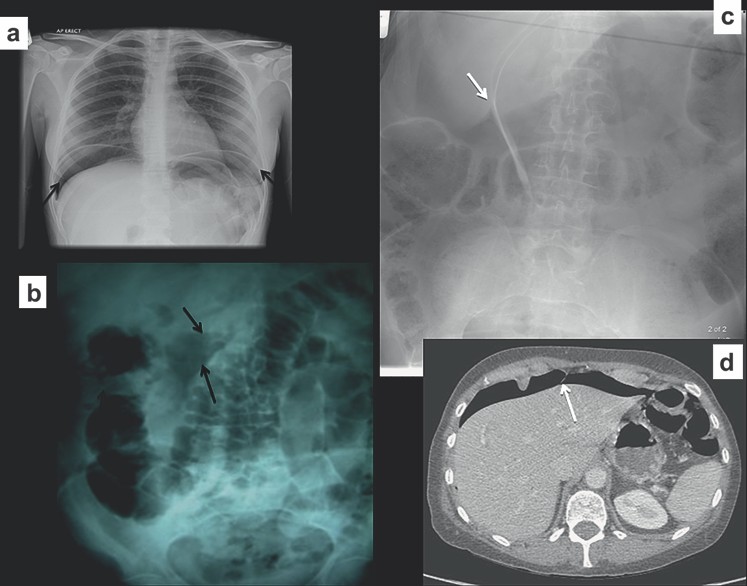

Dạng đơn giản và phổ biến nhất của khí ngoài lòng ruột là khí trong ổ bụng (pneumoperitoneum). Hiện tượng này bao gồm bất kỳ khí do nguyên nhân nào ở trong ổ bụng, điển hình do tạng rỗng chứa khí bị thủng. Thủng tá tràng và đại tràng sigma là thủ phạm thường gặp, nhưng cần xét tới các nguyên nhân khác như mới phẫu thuật, sau thủ thuật (nội soi ổ bụng, chụp tử cung vòi – trứng) hoặc sau đặt các dụng cụ như dẫn lưu lọc màng bụng liên tục. Khí phúc mạc dễ phát hiện trên phim X quang ngực đứng, do đó thường yêu cầu chụp phim ngực đứng hoặc ngồi kết hợp với phim X quang bụng (nằm ngửa). Tuy nhiên, có một số dấu hiệu đã được miêu tả rõ trên phim X quang bụng nằm ngửa. Những dấu hiệu khí phúc mạc gồm có khí dưới vòm hoành, dấu hiệu Rigler, dấu hiệu dây chằng liềm, dấu hiệu tam giác khí, dấu hiệu quả bóng và dấu hiệu vòm hoành liên tục.

Khí dưới vòm hoành là dấu hiệu trên phim ngực đứng hoặc ngồi, dấu hiệu dây chằng liềm và Rigler là các dấu hiệu X quang bụng (tư thế nằm ngửa) phổ biến nhất của thủng tạng rỗng. Dấu hiệu Rigler còn được biết dưới tên gọi “dấu hiệu thành kép”, bởi vì thành ruột nhìn rõ hơn do khí viền ở cả bên trong (khí trong lòng) và bên ngoài (khí phúc mạc). Dấu hiệu dây chằng liềm hình thành do khí viền ở hai mặt của dây chằng liềm là một cấu trúc bình thường không thấy trên phim X quang bụng. Dấu hiệu tam giác xuất hiện khi khí phúc mạc bị kẹt giữa các quai ruột đối nhau (Hình 14 và 15). Dấu hiệu quả bóng do khí tự do có hình dạng giống quả bóng nằm ở phần cao của ổ bụng.

Hình 14. Các dấu hiệu của tràn khí ổ bụng (a) Khí tự̣ do dưới vòm hoành trên phim chụp ngực đứng. (b) Khí tự do hình tam giác trong ổ bụng. (c, d) Dấu hiệu dây chằng liềm trên phim chụp X quang bụng và xác định bằng CT.

Hình 15. Các dấu hiệu của tràn khí ổ bụng (a) Dấu hiệu Rigler biểu hiện khí ở trong và ngoài thành ruột (b) Chụp X quang bụng nằm nghiêng trái chứng minh có ít khí tự do tụ trong ổ bụng.

Thủng vào sau phúc mạc

Hiếm hơn, khí tự do có thể ở khoang sau phúc mạc. Hiện tượng này do thủng chọn lọc ở đại tràng sigma và tá tràng, đặc biệt do nội soi mật-tụy ngược dòng. Khí sau phúc mạc được nhận ra bởi vì nó viền quanh thận hoặc cơ đái chậu (Hình 16).

Hình 16. Khí tự do sau phúc mạc (a) Chụp X quang bụng thấy khí viền ở bên cơ đái chậu trái (b) Chụp CT thấy khí tự do ở tiểu khung sau soi đại tràng sigma bằng ống soi cứng gây thủng. (c) Khí lan sau phúc mạch bao quanh thận trái.